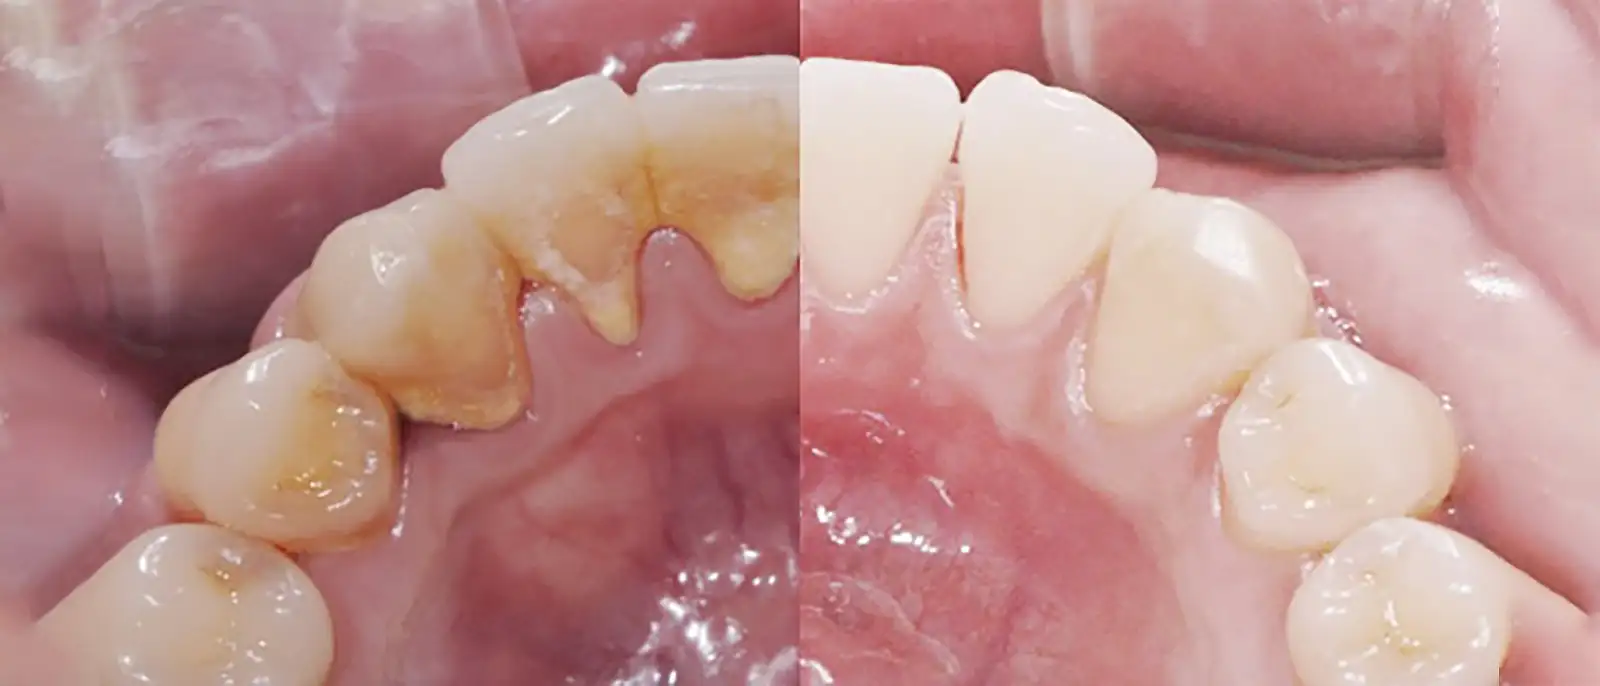

스케일링 하기 전(왼쪽)과 하고난 후(오른쪽)

치아 표면의 치태(플라그)는 이틀이 지나면 굳기 시작하여 2주 만에 딱딱한 치석이 됩니다. 치석과 치태는 충치균의 아파트입니다.

치석은 양치질로 제거되지 않습니다. 치과에서 스케일러로 깨뜨려서 떼어내야 합니다.

초음파 스케일러를 사용하여 치석을 제거하는 시술이 스케일링입니다.